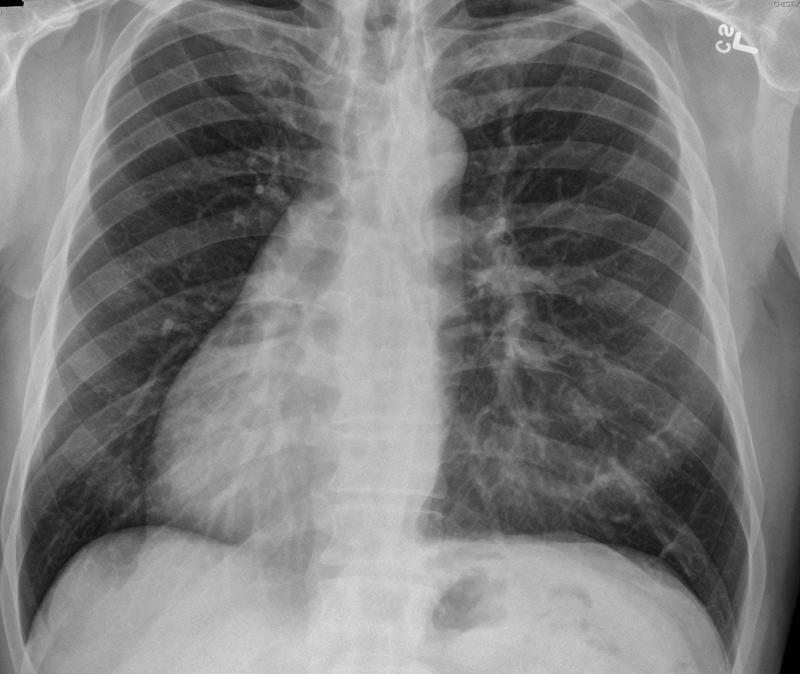

Congenital

Situs inversus